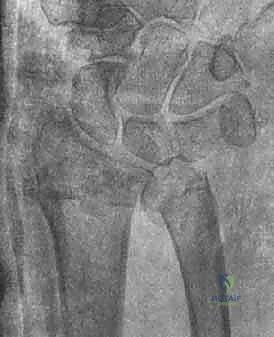

1. الأشعة السينية (X-rays): بوضعيات متعددة (أمامية خلفية، وجانبية دقيقة). الوضعية الجانبية الحقيقية (True Lateral) حاسمة لاكتشاف أي خلع جزئي في المفصل (DRUJ).

2. الأشعة المقطعية ثلاثية الأبعاد (3D CT Scan): تُستخدم في الكسور المفتتة أو كسور رأس الزند المفصلية المعقدة، حيث تعطي خريطة دقيقة للجراح قبل الدخول لغرفة العمليات.